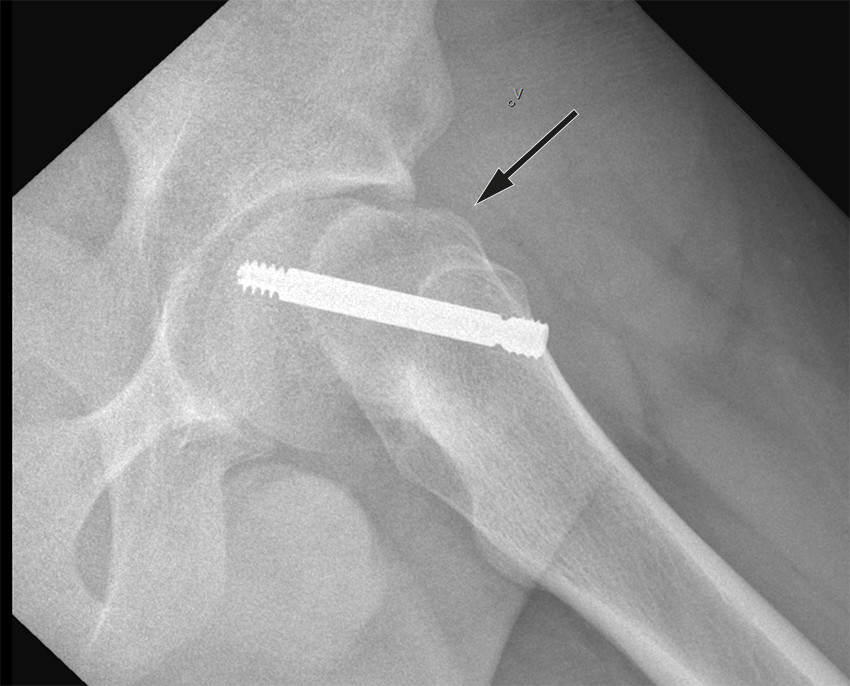

Standard behandling er operativ stabilisering av epifyseskiven. Hensikten er å gjøre pasienten symptomfri samt hindre ytterligere glidning. Epifyseskiven stabiliseres in situ, det vil si man gjør ingen forsøk på å reponere glidningen. Imidlertid vil en del av feilstillingen kunne reponere seg spontant ved ustabil epifysiolysis capitis femoris i forbindelse med leiring under operasjon (figur 2). Grunnen til at det ikke skal gjøres noe aktivt forsøk på reponering er at det gir økt risiko for skade på blodforsyningen til epifysen, med fare for caputnekrose som komplikasjon (11).